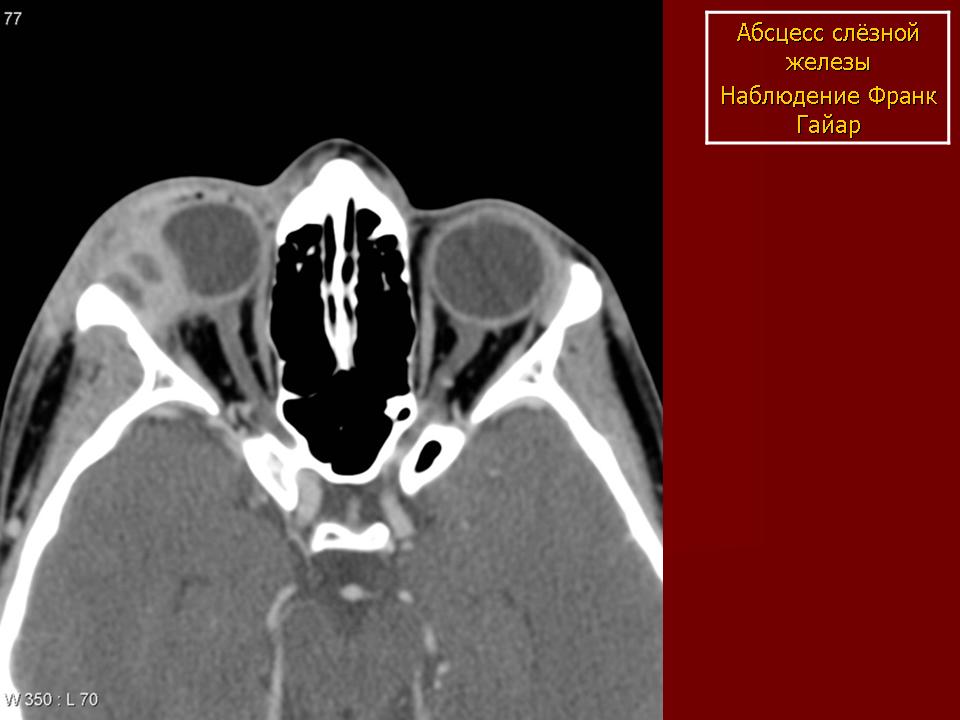

Воспалительные заболевания слёзных путей.